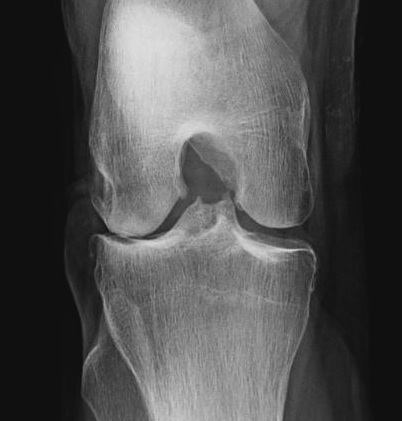

Rosenberg view / tunnel view

- 45o flexion weight bearing view

Rationale

- most early cartilage loss is in 30-60o flexion range

- can be missed with view in extension